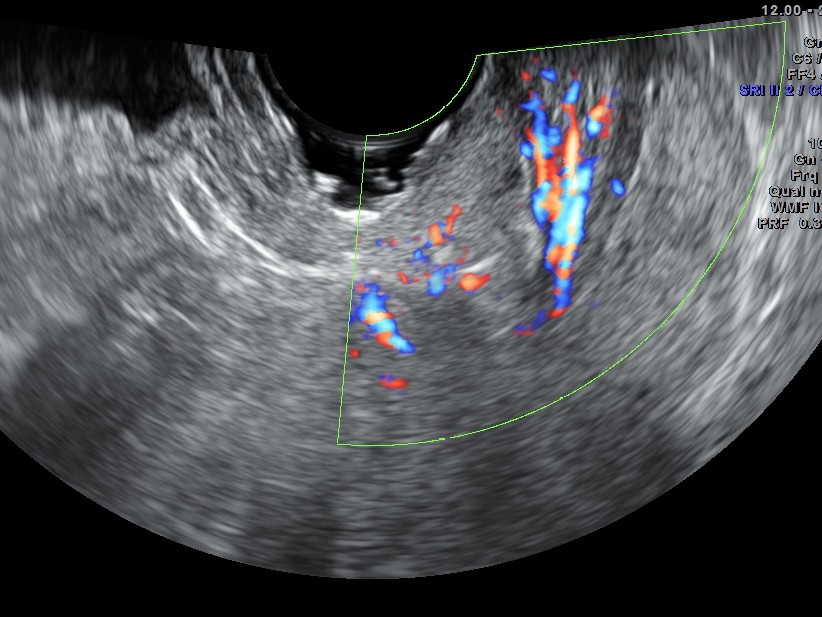

the following images are acquired trans vaginally and the starking difference in clarity can be appreciated.

the multi planar 3 d image shows increased flow in the polyp and the stalk arising from the endometrium

The diagnosis offered was an endometrial polyp with a long stalk situated in the cervix.